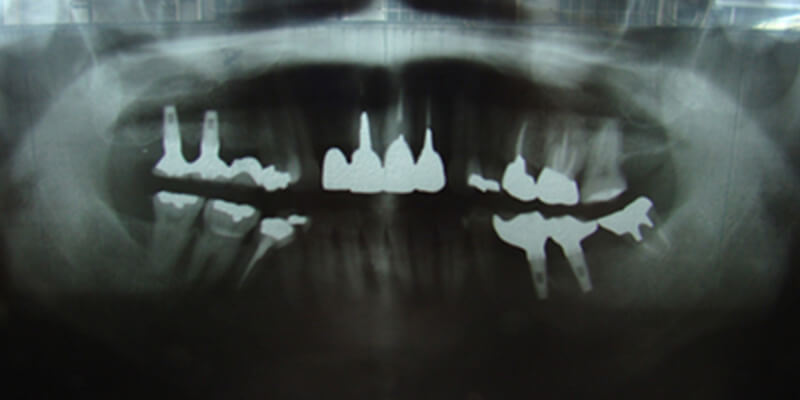

![]() | 奥歯が3本抜けてしまった状態です。従来はブリッジや入れ歯で治療していましたが、それでは残っている歯に負担がかかってり 、傷つけたりしてしまいます。 |

![]() | 残っている歯のために、インプラント治療を選びました。まず、歯が抜けてしまったところに、インプラントを植え込むためのスペースを作ります。 |

![]() | インプラントを植え込むためのスペースにもともとあった歯の形に合わせたインプラントを植え込みます。 |

![]() | インプラントを植え込んだら、歯肉で蓋をして約3ヶ月~6ヶ月待ちます。この期間を治癒期間と呼び、この間にインプラントが顎の骨と一体になります。 |

![]() | インプラントと顎の骨が一体になったら、インプラントに支台装置を取り付けて人工の歯をかぶせます。 |

![]() | インプラントによる補綴(歯の再建)処置が完成した状態です。歯があったときと同じ感覚が回復します。残ってい歯の状態も良くなります。 |

![]() | 完成です。 ※治療後について インプラントは人体との親和性に優れ、腐食しにくいチタン素材を使用していますが、治療後の清掃を怠りますと天然歯と同様に歯槽膿漏になり抜け落ちることもあります。定期的に健診を受けることがインプラントを長持ちさせる秘訣です。 |